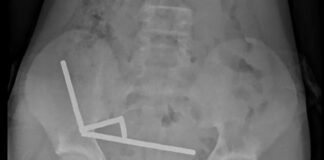

Paciente perde a vida depois de pinça esquecida em procedimento cirúrgico

2 de janeiro de 2026